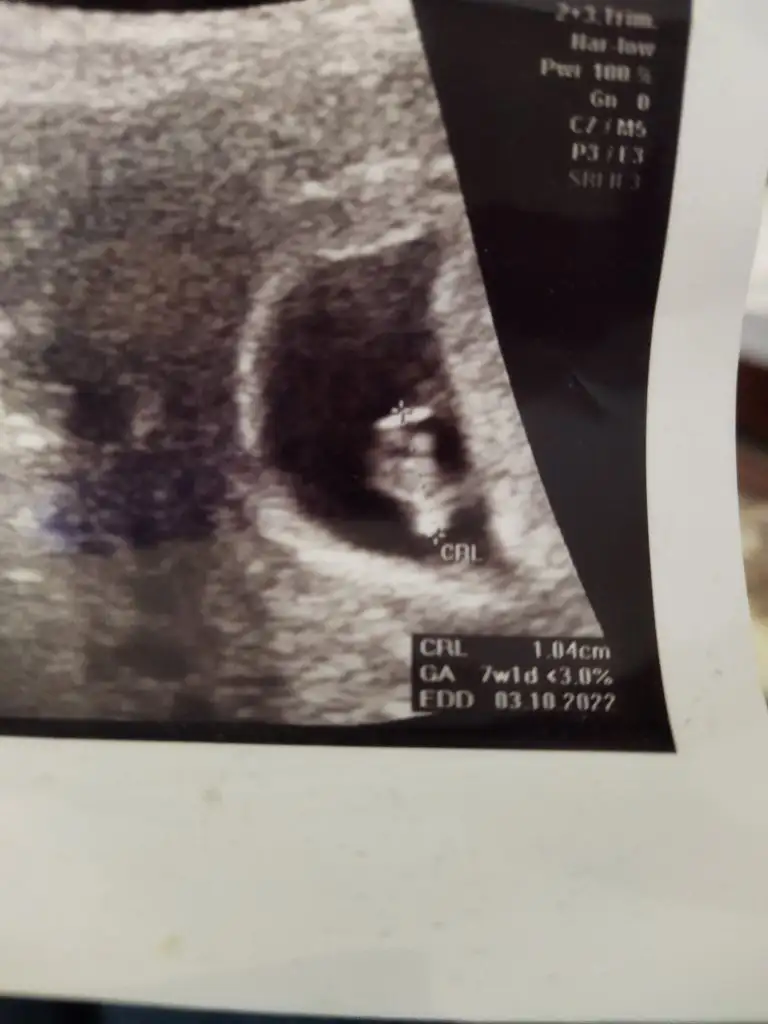

Merhaba! Kizlar arkadaşım ilk bebeğine hamile ona da tahminde bulunabirmisiniz😍 7+3…. Teşekkürler💐

Eklentiler

• 704EBC99-69B3-45EE-9F1E-23D50745E839.webp

704EBC99-69B3-45EE-9F1E-23D50745E839.webp

23,9 KB · Görüntüleme: 83